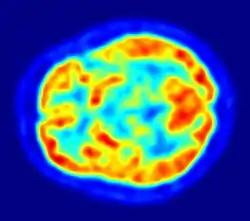

Les neurophysiologistes étudient les propriétés chimiques, pharmacologiques et électriques du cerveau. Leurs principaux outils sont les drogues et les dispositifs d'enregistrement. Des milliers de drogues expérimentalement développées affectent le système nerveux, plusieurs le font de manière très spécifique. L'enregistrement de l'activité cérébrale peut se faire par l'utilisation d'électrodes, soit collées au crâne comme dans le cas d'électro-encéphalographie, soit implantées à l'intérieur du cerveau pour des enregistrements extracellulaires, qui peuvent détecter les potentiels d'action générés par des neurones individuels. Comme le cerveau ne contient pas de nocicepteurs, il est possible d'utiliser ces techniques sur un animal éveillé sans causer de douleur. Il est aussi possible d'étudier l'activité cérébrale par un examen non invasif en utilisant des techniques d'imagerie fonctionnelle comme l'IRM. Ainsi la tomographie à émission de positons met en évidence qu'en l'absence de toute focalisation particulière de l'attention, l'activité du cerveau (activité intrinsèque du réseau du mode par défaut, nommée « énergie sombre du cerveau » par analogie à l'énergie sombre du cosmos[82] et qui consiste en des vagues d'ondes électriques lentes) correspond à une dépense de 60 à 80 % de toute l'énergie consommée par le cerveau, soit une énergie 20 fois supérieure à celle consommée par le cerveau lorsqu'il réagit consciemment, la réalisation d'une tâche particulière (activité consciente moins fréquente que l'activité inconsciente) exige une énergie qui n'excède pas 5 % de celle consommée par l'activité de fond[83].